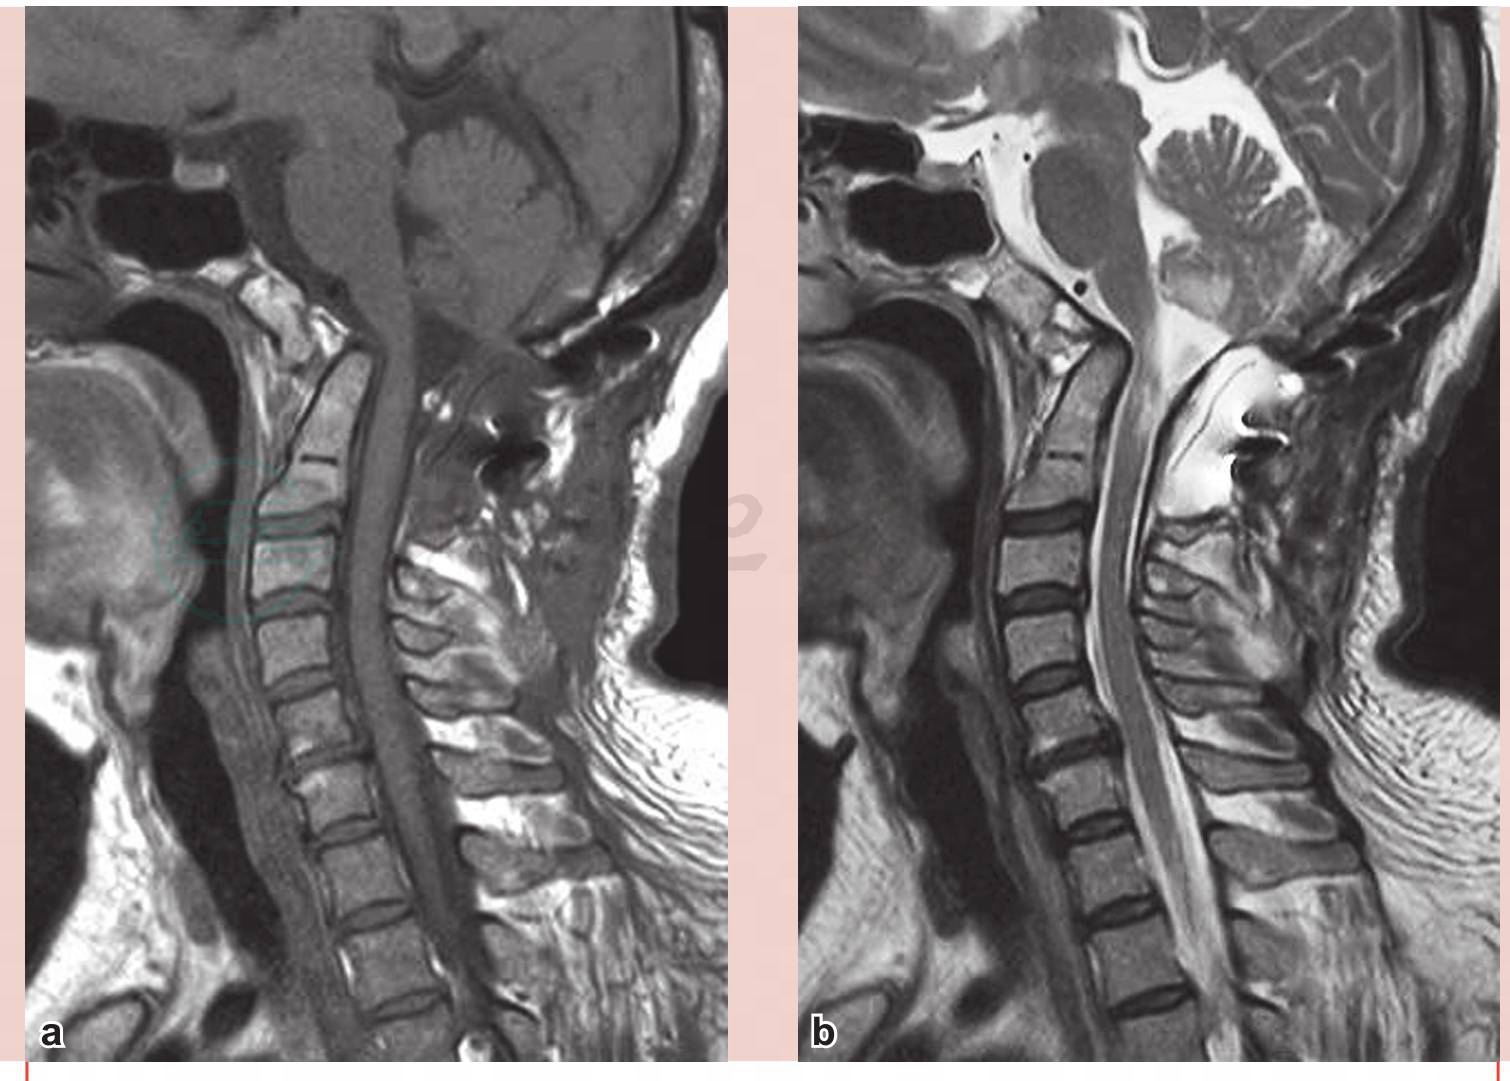

术后患者恢复良好,神清语利,刀口愈合良好,双侧瞳孔等大等圆,直径约3.0mm,对光反应灵敏,四肢肌力Ⅳ+级,肌张力略高。右手活动较前灵活,骨间肌力量增加。术后复查颈椎MRI及CT,提示齿状突较前下移,寰齿间隙较前变小,脊髓空洞变细(图6)。脑脊液电影示中脑导水管、第四脑室脑脊液流动信号较术前增强(图7)。术后CT示齿状突较术前下移明显(图8),C2椎弓根螺钉位置良好(图9),寰齿间隙缩小(图10)。术后半年复查颈椎MRI示脊髓形态良好,脊髓空洞基本消失(图11)。磁共振(MRI)脑脊液电影显示桥前池、中脑导水管、第四脑室及枕骨大孔脑脊液流动基本正常(图12)。

图6 术后磁共振(MRI)示脊髓空洞明显缩小

a.T1像;b.T2像

图11 术后半年复查磁共振(MRI)示脊髓空洞基本消失